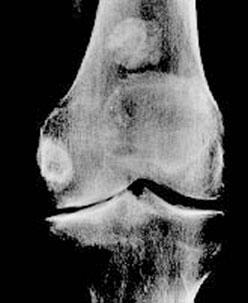

Cent dix-neuf personnes avec une arthrose de l'articulation des doigts ont été suivies pendant trois ans. Elles ont reçu, trois fois par jour, 400 mg de sulfate de chondroïtine ou un placebo. Des radiographies des articulations ont été faites au début de l'étude, puis une fois par an. À la fin de l'étude, le nombre de patients dont la maladie avait progressé était nettement moins important dans le groupe traité avec le sulfate de chondroïtine que dans celui sous placebo (Verbruggen et al., 1998).